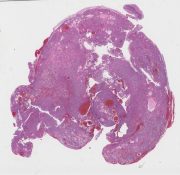

AANP2006-2.svs

28660 x 24077

@ 20X